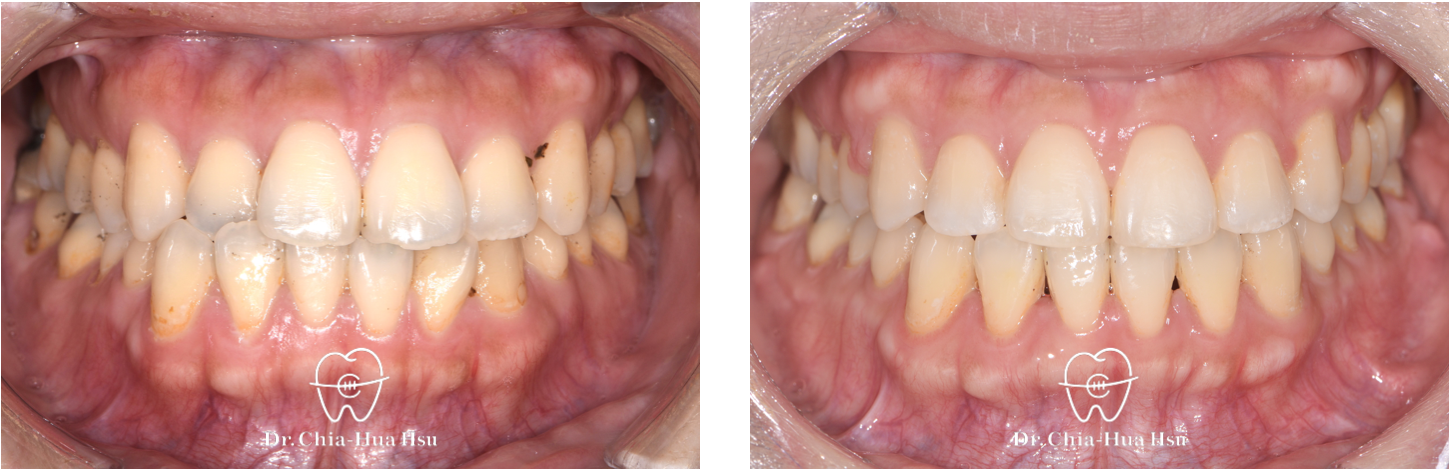

錯咬、齒列擁擠

成人矯正 | ⾦屬矯正 | 非拔牙治療 | 骨釘

治療前

治療後